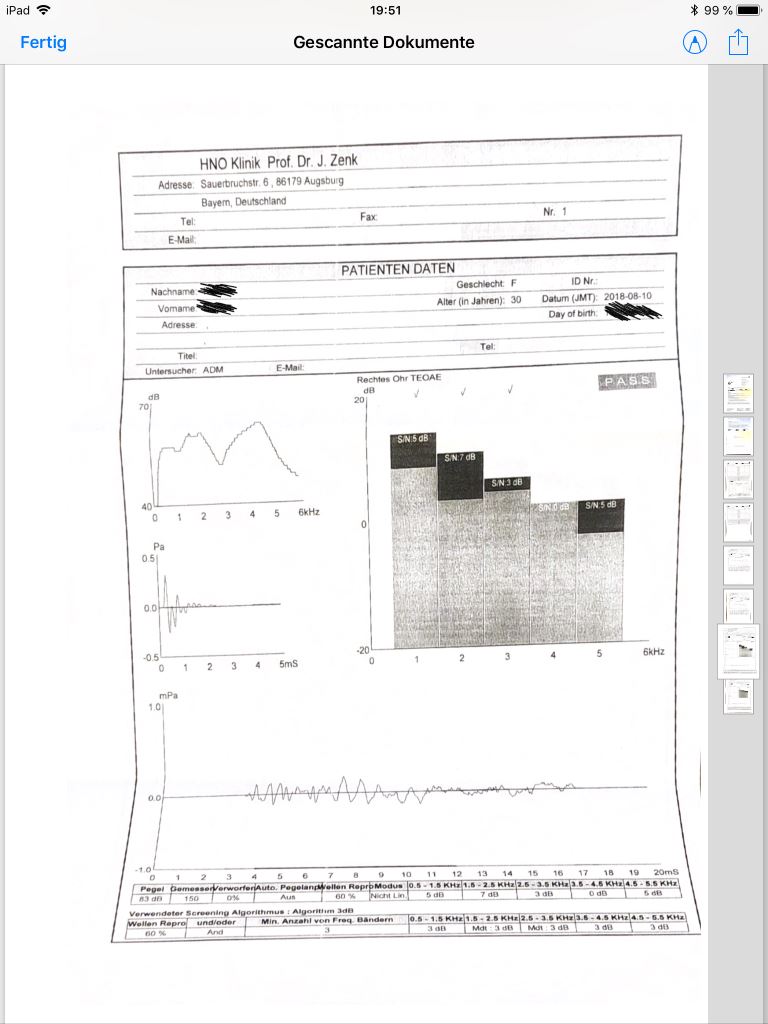

ich war bis heute stationär im KH wegen einem Hörsturz. Es ist wohl so dass ich auch noch eine Schwerhörigkeit habe, wobei lt. der Dame die die Tests gemacht hat die Ergebnisse nicht zusammenpassen. Leider kenne ich mich mit den Testergebnissen gar nicht aus und der Arzt meinte erst mal abwarten. Kann mir jemand aus dem Forum vllt. Die Ergebnisse erklären?

zunächst einmal ist es so, dass von den Werten für das rechte und das linke Ohr her gesehen eine grosse Aehnlichkeit besteht.

Auffällig in Bezug auf die Ergebnisse der Reintonaudiometrie (Du musstest bei diesem Test Dir Töne anhören und signalisieren, sobald Du sie hörst) ist die Kurvenform: es sind alle Frequenzen von einem Hörverlust betroffen, insbesondere jedoch auch die tiefen und am stärksten die mittleren (genau bei 1 kHz). In der Mehrzahl der Fälle sind die hohen Töne besonders stark betroffen.

Die Sprachtests ergeben erstaunlich gute Werte - Sprache scheinst Du trotz der deutlich erhöhten Hörschwellen ziemlich gut zu verstehen.

Besonders ist auch, dass die Ergebnisse der TEOAEs und die DPOAEs mehr oder weniger unauffällig sind.

Diese Tests sagen (bei intakter Mittelohrfunktion, welche bei Dir auf Grund der Resultate gegeben sein muss) aus, dass die OHCs im Innenohr mehr oder weniger intakt sind. Da, wie bereits erwähnt, auch keine Schallleitungsproblematik vorhanden ist, muss die Hörstörung ihre Ursache "irgendwo ab den inneren Haarzellen im Innenohr" haben - das heisst, dass diese Zellen, der Hörnerv oder auch die Hörbahnen im Hirn einer Funktionseinschränkung unterliegen könnten.

Da dies für beide Ohren gilt, kann man sich auch fragen, weshalb bei rechten Ohr die Störung plötzlich aufgetreten ist, beim linken jedoch (vermutlich) schleichend.

Als weitere Untersuchung käme für mich auch eine Ueberprüfung der Stapediusreflexe (möglichst umfassend) und diverse BERAs (Hirnstammaudiometrie) in Frage.

die Ton- und Sprachaudiogramme passen überhaupt nicht zueinander.

Nach Tonaudiogramm hörst du zB rechts erst ab 50dB etwas, verstehst aber schon 50% der gesprochenen Worte bei einer Lautstärke von 50 dB, sogar Zahlen verstehst du unterhalb der Hörschwelle, dh du verstehst Zahlwörter bevor du bei gleicher Lautstärke noch keinen Ton wahrnimmst.

Das stimmt (so genau habe ich mir das dann nicht angeschaut). Die im Bericht erwähnten Hörschwellen liegen auch tiefer als die im Audiogramm eingetragenen.

Übertragen würde man bei deinem Sprachaudiogramm Hörschwellen um die 25-30 dB im Tonaudiogramm erwarten. Dieses würde auch zu den anderen Tests wie den OAEs passen.

Daher wohl die Vermutung der Ärzte, dass du deutlich besser hörst als es das Tonaudiogramm vermuten lässt und die Empfehlung, den Test zu wiederholen und beieiner Verschlechterung des Hörverstehens Hörgeräte anzupassen - diese sind nämlich noch nicht indiziert, da du beidseitig bei 65 dB 100% verstehst!